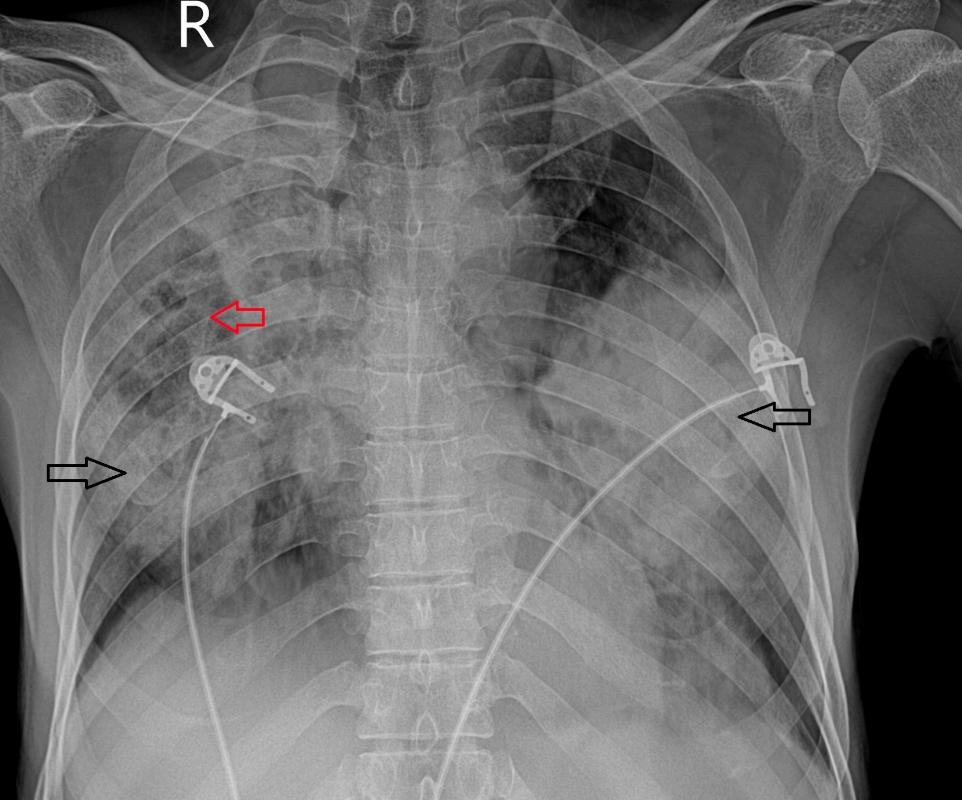

PA胸片示双肺大面积融合实变,右中部实变内可见少量透亮区。胸部CT平扫

显示双肺广泛实变,其间有磨玻璃影、间隔增厚及多发小囊性/空洞区。部分实变显示内部低密度区(衰减值范围为15-25 HU)。无胸腔积液

或明显的纵隔淋巴结肿大。

图1 PA胸片示双侧肺实变(黑色箭头),右中部可见多发囊性透亮区(红色箭头)。